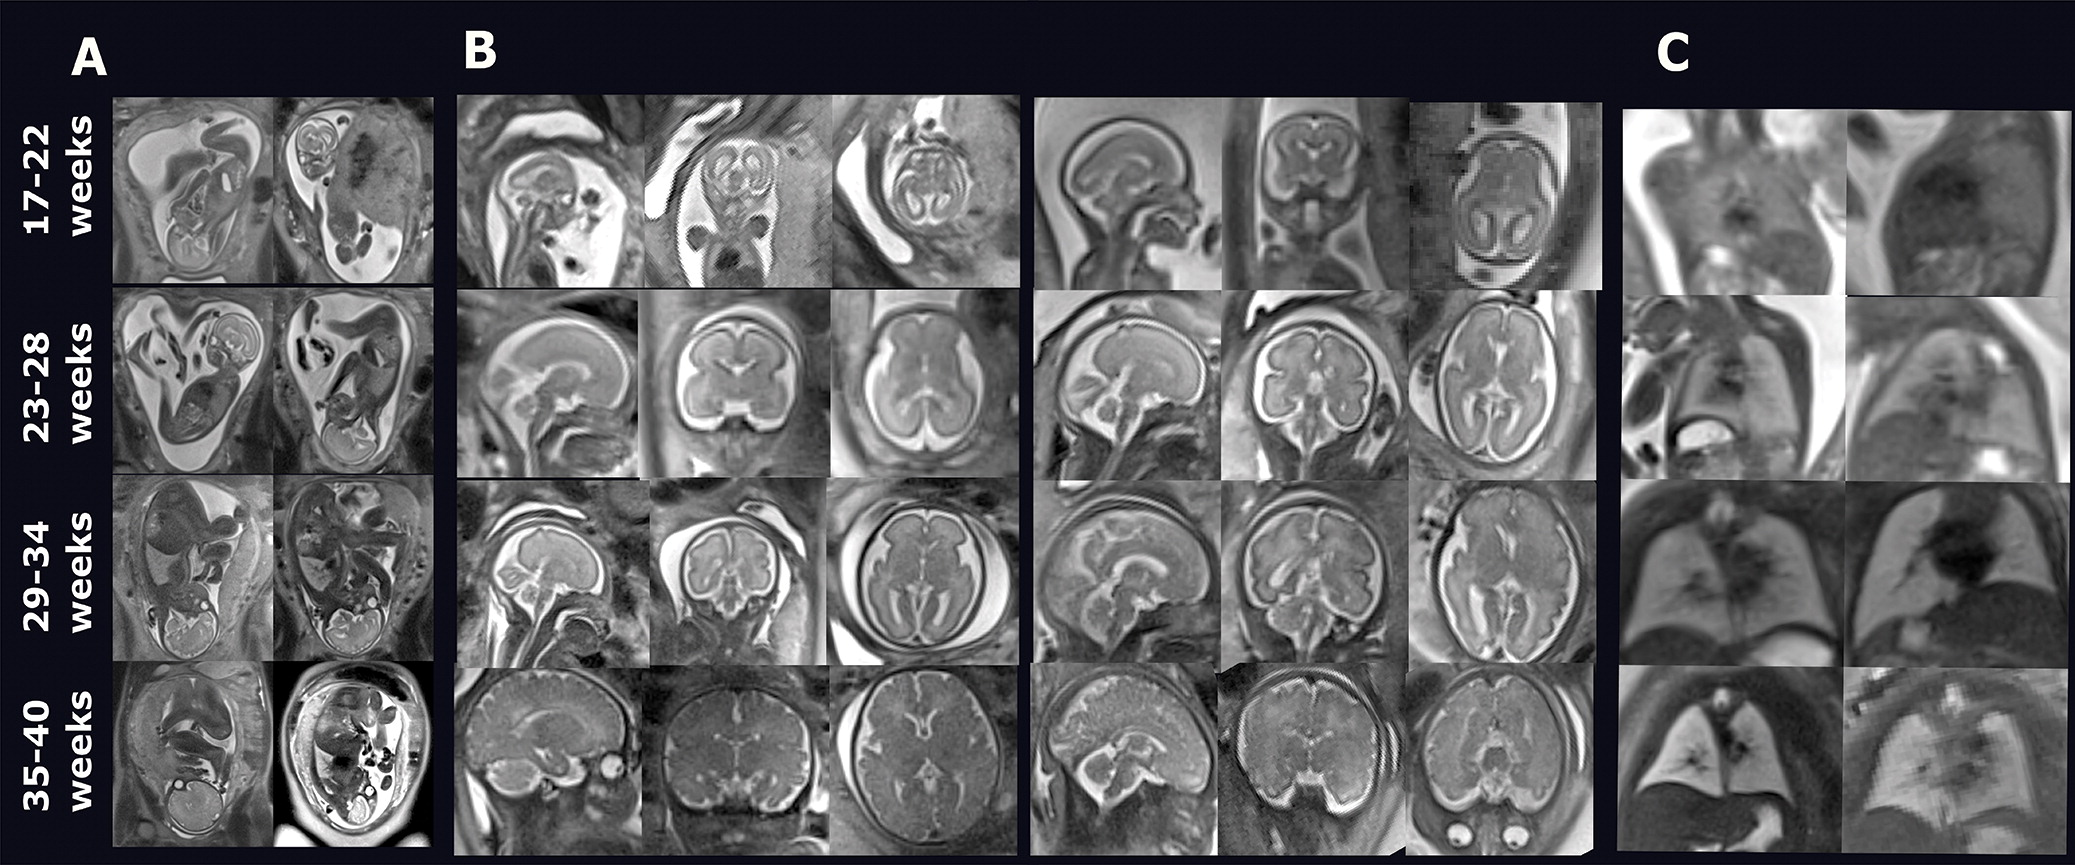

To address this knowledge gap, Nagaraj's group conducted a study that included 65 women in their third trimester of pregnancy who underwent fetal MRI exams between July 2020 and December 2021. Of the 65 fetuses, 28 had been exposed to opioids. The investigators tracked 14 biometrics of fetuses' brains and adjusted the results for gestational age, fetal sex, and exposure to nicotine.